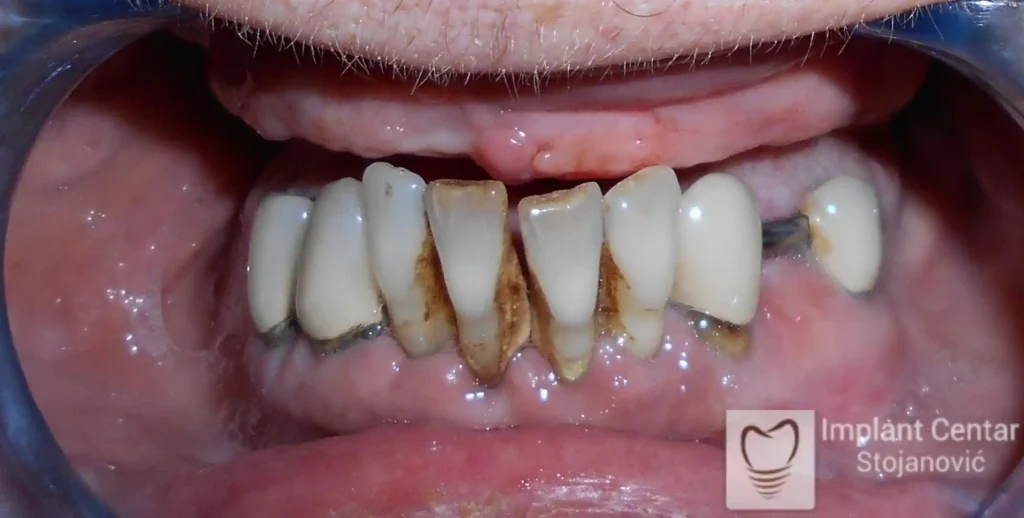

Na slici 1. i slici 2. prikazan je izgled pacijenta pre početka terapije – klinički i rendgenološki.

Nakon vađenja zuba, ugrađeni su implantati. Na slici 3 prikazan je ortopan snimak sa ugrđenim implantatima. Tokom perioda osteointegracije, pacijent je bio zbrinut fiksnim privremenim krunicama na implantatima, koje su izrađene samo dva dana nakon hirurške intervencije.